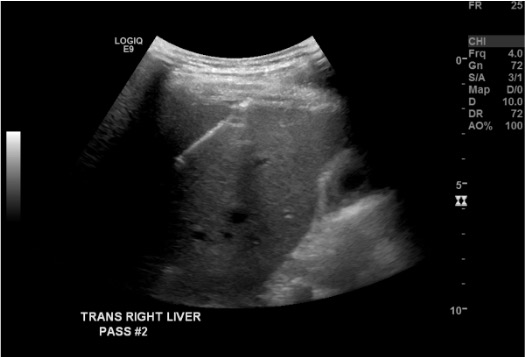

View needle positioning

Ultrasound showing biopsy needle positioned in liver target